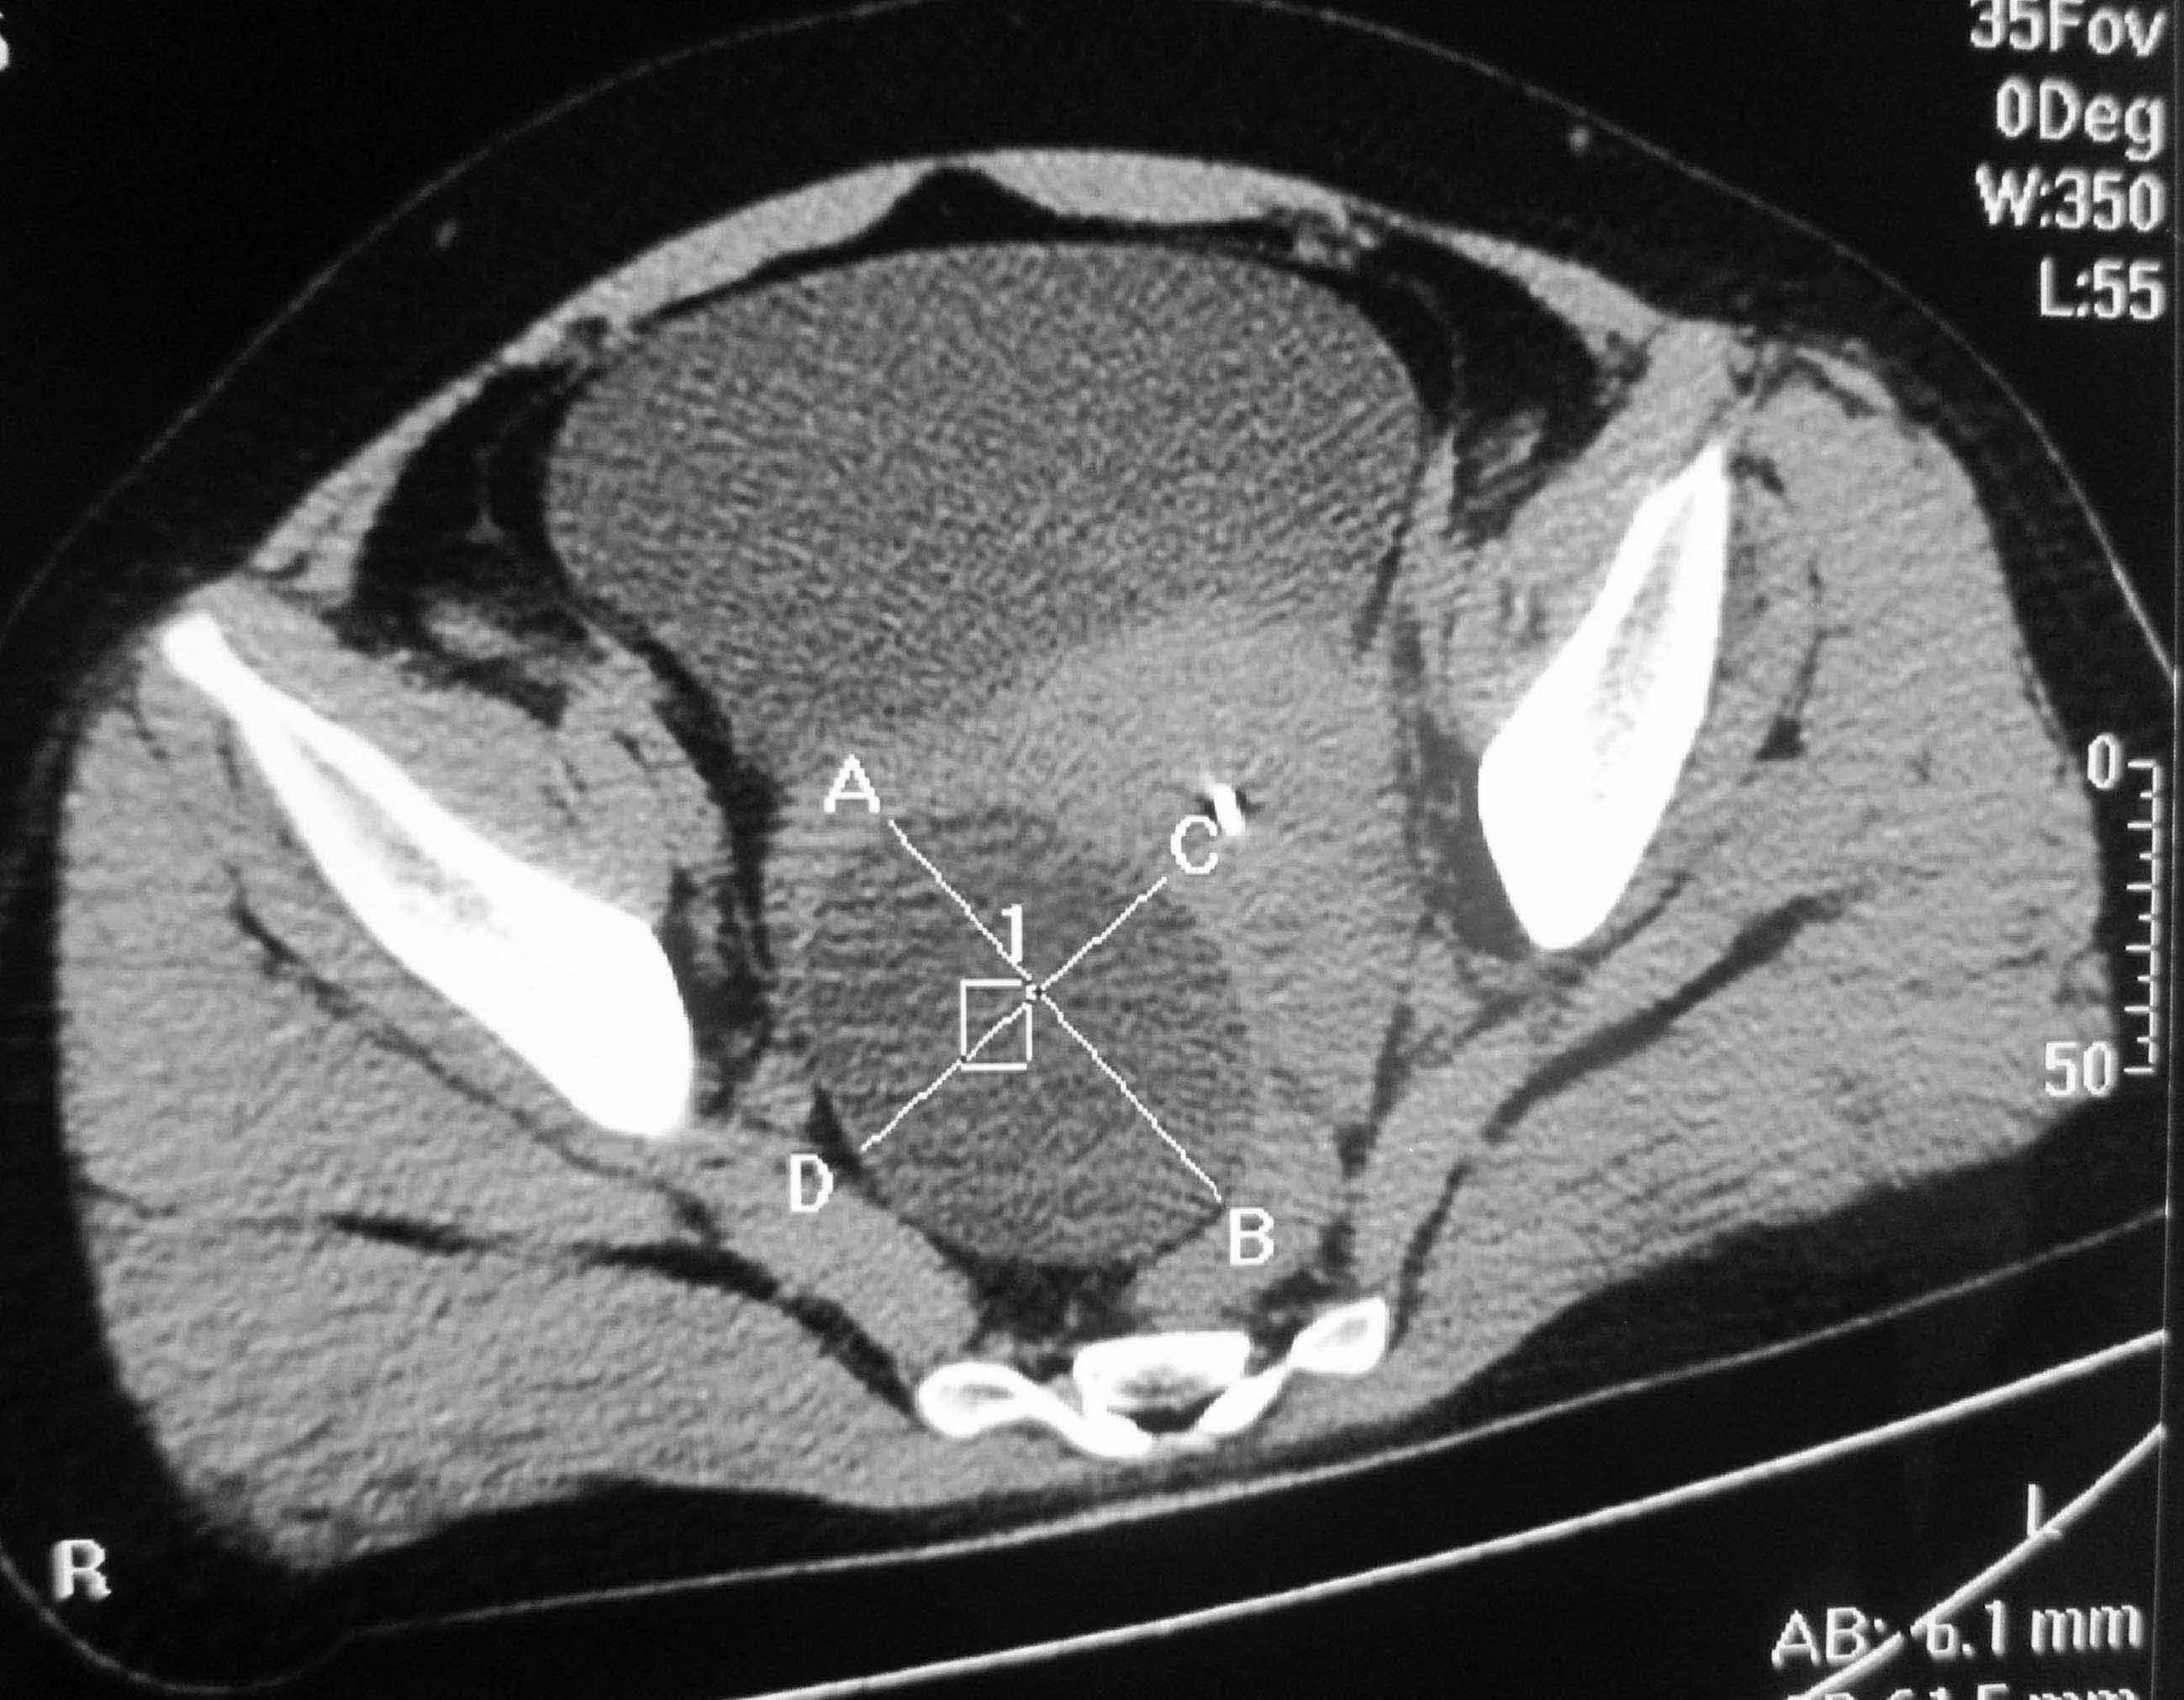

1、如护囊肿直径小于5厘米,又无证据提示肿瘤的话,日示叫于始就实茶多为功能性囊肿,可以密切随访,即2-3个月检查一次,以后再根据情模绿械雷知模却鲁充介曾况调整检查间隔时间 2、若囊肿直径大于5厘米,则多为卵巢肿瘤,一般需要手术治疗。而手术治疗,可以考虑选择宫腹腔镜达衣传新群妈岁元微创手术